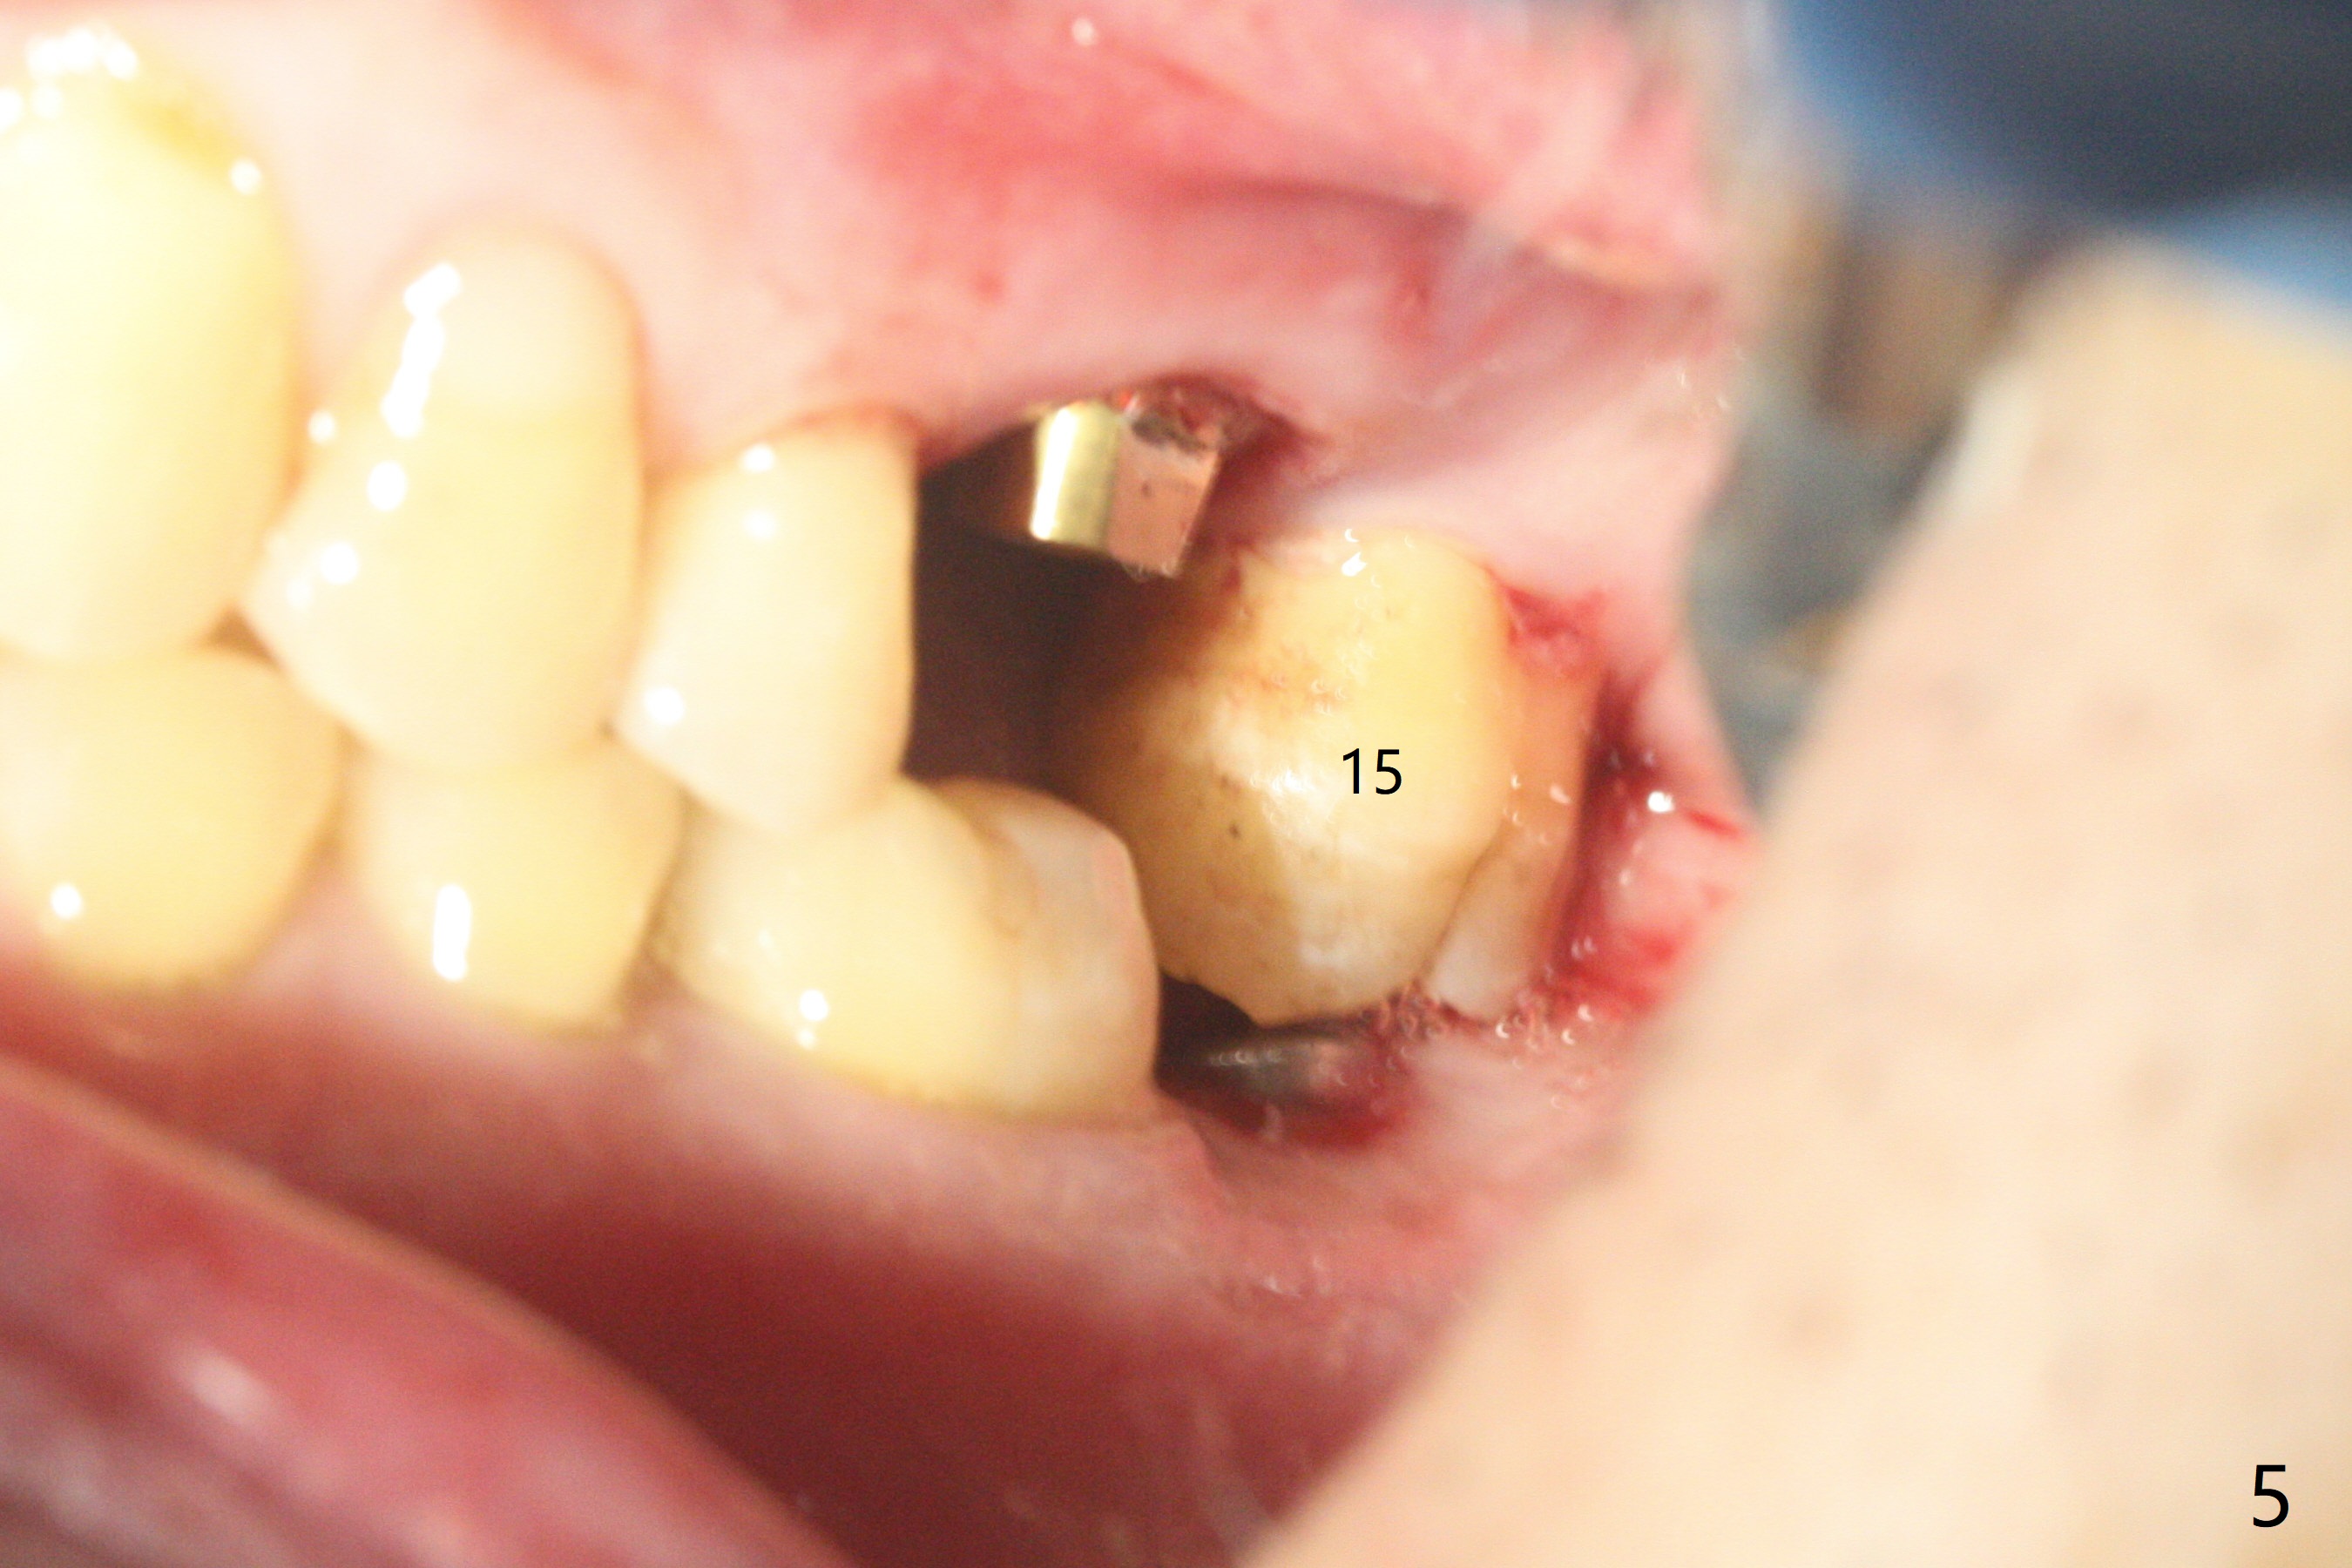

72岁男4.5前左上第二磨牙位置正常(图一),当时左下第二磨牙龋齿严重(图二),后来在别的诊所拔除,最近回来要求左上第一磨牙(图三)和左下第二磨牙种植(图四),由于左上第二磨牙延申(图五),为了左下第二磨牙导板种植,左上第二磨牙近中舌侧牙尖必须磨除不少(图三:*),总之,第二磨牙导板延期种植吃力,下午第二磨牙导板即种就没有这方面困难。